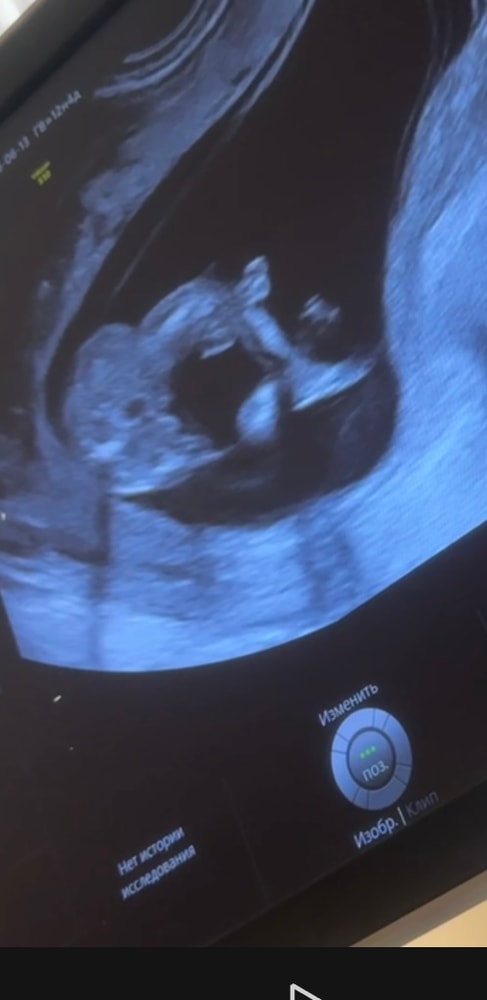

2 фото - закинул ножку на ножку, вид со стороны попы (снизу)

Что видите на 2 фото, мальчик, девочка? Я пока ничего, через 8 дней на НИПТ узнаю точно 100%

Похоже на девочку, жалко нет фото сбоку во весь рост. Но думаю, девочка

Кактусеныш, блин, я часами уже смотрю и думаю, это ведь не похоже не пенис? Потому что как будто похоже 😆😭

Mia, да нет) Скорее «пирожок» вижу

Но могу ошибиться. Но это точно не пенис))